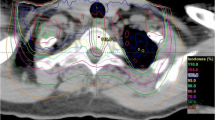

Representative MR-images for the biological endpoint paresis grade II after carbon ion (12C–ion) and photon irradiation compared to an untreated control. The symptomatic animals show an edema (white arrowheads) and canalis centralis dilatation (red arrowhead) in the T2-weighted images as well as contrast agent (CA) accumulation in the T1-weighted images (lowest row, white asterisks)

After carbon ion as well as after photon irradiation histological examinations of the endpoint paresis grade II revealed a comparable extent of tissue damage (Fig. 4). Compared to the unirradiated control, a structural decline in terms of white matter vacuolization, necrosis, blood vessel dilatation and disruption was found in the posterior and lateral part for both radiation modalities. A clear demyelination represented by the loss of luxol fast blue staining has been seen after photon irradiation (Fig. 4c). The blood vessels in the grey matter were dilated and perforated whereas the overall structure remained visually intact. However, a larger extent of blood vessel perforation was found after carbon ion than after photon irradiation. The albumin extravasation, represented by a brown precipitation, was more intense after carbon ion irradiation, predominately in the dorsal part of the white matter and around the canalis centralis whereas after photon irradiation the albumin extravasation was found to be weaker in these areas (Fig. 4).

Histological sections representative for the biological endpoint paresis grade II. Cryosections stained with hemalum/eosin in combination with Luxol fast blue (a-c). A clear structural decline in the white matter represented by necrosis (asterisk) and vacuolization (open arrows) as well as hemorrhages (white arrows) and dilated blood vessels (closed black arrows) can be seen (b, c). Paraffin sections for detection of albumin extravasation (brown precipitation) combined with Nissl staining (d-f). Albumin leaks predominately in the area where structural decline of white matter occurs (black asterisks) and around the canalis centralis (white arrow heads). The leakage is more intense after carbon ion (e) than photon irradiation (f) (scale bar 200 μm)

The MRI-based longitudinal study enables a non-invasive investigation of occurring radiation-induced effects during the symptom free latency time. We found a fixed sequence of alterations in the images. Comparing the carbon ion and photon irradiations at isoeffective doses with respect to the endpoint paresis grade II, the same morphological changes were found and the only difference was a shorter latency time after carbon ion irradiation. Main findings in MRI were presence of edema, syrinx, uptake of contrast agent due to the break-down of the BSCB and finally followed by paresis grade I and II. Once the edema occurred in an animal, it developed the deterministic sequence. These findings were also confirmed quantitatively by evaluation of the DCE-measurements, which showed that the increase of the extracellular volume, ve, and the contrast agent exchange rate, Ktrans, increased similarly for carbon ions and photons.

At the endpoint paresis grade II, histological examinations revealed a comparable breakdown of the tissue structure for both radiation modalities; however, the increase of blood vessel permeability was much higher after carbon ion irradiation. This finding is in contrast to results of the DCE evaluation, where no difference was seen at the same endpoint.

It has to be noted, however, that increased permeability of the BSCB was detected with albumin, which presents a much larger molecule than MRI contrast agent Gd-DTPA (66 vs. 0.5 kDa). The discrepancy between the results of MRI and histological analysis could therefore be explained by a different extent of perforation for the two irradiation modalities. While the higher ionization density of carbon ions introduces more complex, non-reparable DNA-damage, which leads to intense blood vessel perforation and thus to an increased permeability for Gd-DTPA as well as for albumin, photons exhibit a low ionization density which induces better reparable DNA-damage and leads only to small vessel perforations and thus to an increased permeability for Gd-DTPA but much less for albumin. To clarify this, additional histological investigations with smaller molecular markers are required.

Besides vascular changes, also a profound damage of the neuronal structures was observed. Luxol fast blue staining shows a clear decrease of the myelin basic protein at the biological endpoint paresis grade II. To assess the relative importance of vascular and neuronal damage, a detailed investigation of the temporal development of both structures on the histological and molecular level will be performed within the ongoing MRI-based histological study.